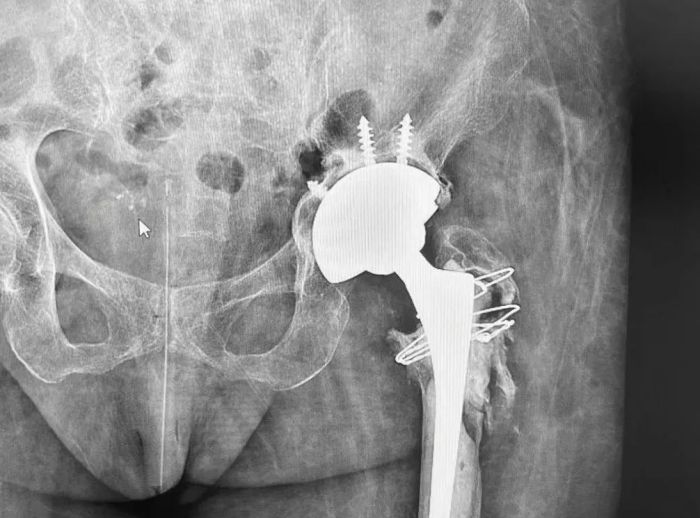

毛新展教授主刀为患者施行全髋关节假体翻修术

在医院麻醉团队的密切配合下,经过数小时的精细操作,毛新展教授为患者成功施行全髋关节假体翻修术(左)。患者坏死病灶被去除,股骨头假体精准复位至髋臼杯内,成功实现了关节的重建与功能恢复。